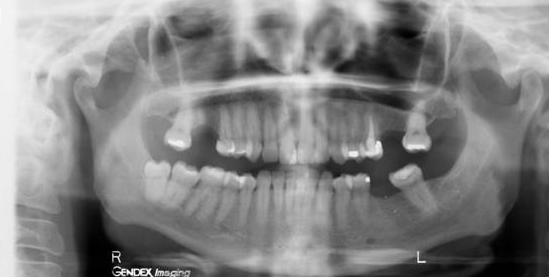

Dilaceration

(Most common in mandibular 3rd molars)